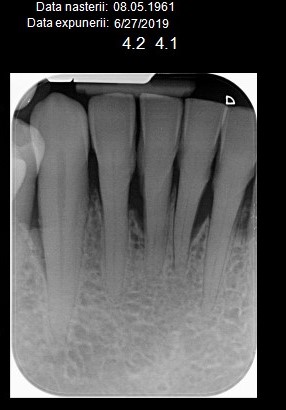

Atașez pozele unui pacient care până la vârsta de 44 ani nu a fost niciodată la dentist, cu reflex de vomă exagerat și igienă deficitară, speriat că i s-a propus extracția a peste 50% din dinți din cauza mobilității generalizate de gradul II și III. Am mers pe varianta clasică, debridare parodontală nechirurgicală, la microscop, cu anestezie locala în toate cadranele, realizată într-o singură ședință. Am administrat antibiotic pe cale generală și am urmărit respectarea indicațiilor de igienă prin controale lunare. Rezultatele la 6 luni vorbesc de la sine, acum putând să ne ocupam liniștiți de regenerarea defectelor osoase de la nivelul 21 22, de altfel singurii dinți care mai au mobilitate.

Iar retracția de la 31 s-a vindecat singură 🙂 Pentru că timpul e, uneori, cel mai bun tratament.